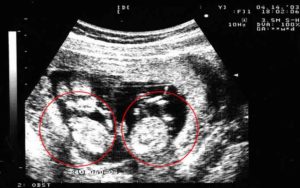

- Ультразвуковое исследование — самый достоверный способ увидеть и определить, какая у женщины беременность, более точный срок беременности, размеры плодов и все патологии, существующие у двоих эмбрионов (если таковые имеются). А также при помощи данного метода возможно определить однояйцевая или разнояйцевая беременность наблюдается у женщины.

Двойню на УЗИ можно увидеть и определить уже на 4-5 неделе беременности. Как правило, однояйцевые близнецы определяются позже, чем разнояйцевые (не раньше 12 недели).